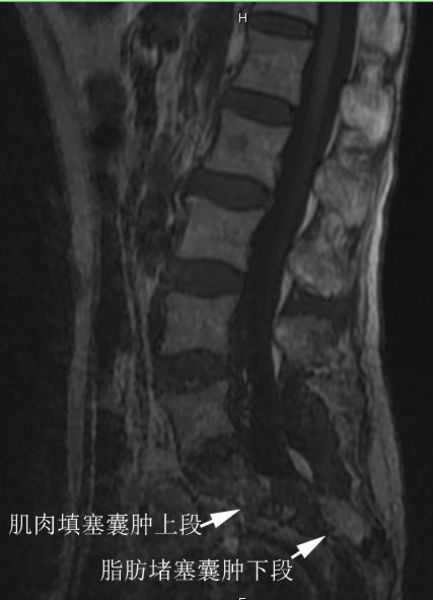

术后磁共振T1相显示,囊肿已经完全封堵了,肌肉(T1显示为灰色)填塞了囊肿的上段,用脂肪(T1显示为白色)填塞了囊肿的下段。囊肿内完全没有脑脊液了。